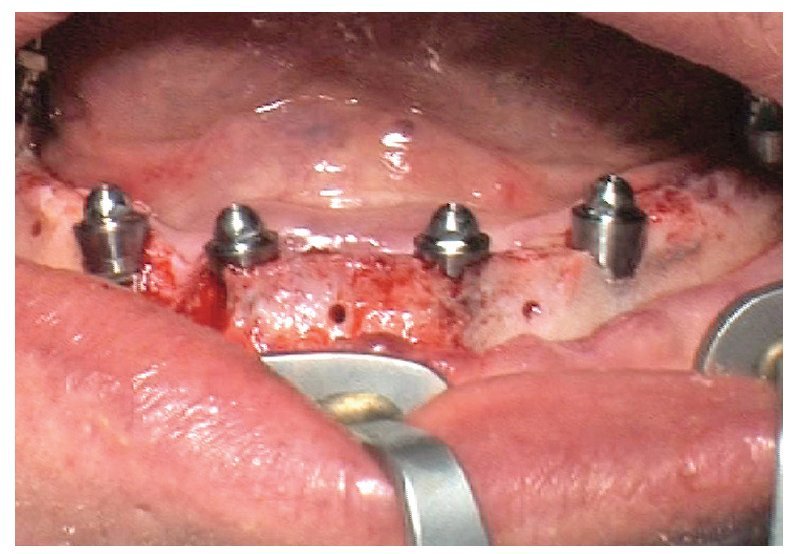

Fig. 70. La prótesis provisional del maxilar inferior se une a los pilares; para ello se alinea a partir de la guía oclusal de la prótesis provisional del maxilar superior.

La intervención quirúrgica (figs. 63 y 64) se realizó bajo anestesia local y se trataron al mismo tiempo ambas arcadas dentarias. Durante la primera fase se insertaron seis implantes cónico-cilíndricos (SPI®CONTACT, Thommen Medical AG, Waldenburg, Suiza) en la arcada dentaria superior mediante un acceso sin colgajo. Para ello se utilizaron los pilares pertinentes para reposiciones de puente atornilladas oclusalmente (VarioMulti, Thommen Medical AG, Waldenburg, Suiza) (fig. 65). Tras la intervención quirúrgica se colocó en boca la prótesis provisional prefabricada a partir de los datos de planificación y tallada en las posiciones de implante y se unió a las cofias provisionales (fig. 66 y 67); para ello se utilizó un composite de fraguado dual. Mediante una prótesis provisional mucosoportada se pudo preservar la estructura gingival hasta el momento de la implantación, y con ello la relación correcta entre los maxilares superior e inferior. Para la arcada dentaria inferior se utilizaron implantes cilíndricos (Element, Thommen Medical AG) (figs. 68 y 69). En combinación con los pilares pertinentes para prótesis atornilladas, se procedió aquí de la misma manera que en el maxilar superior. Una vez se hubo alineado oclusalmente la prótesis provisional del maxilar inferior con respecto al superior, se fijó sobre las cofias provisionales (fig. 70); debido a la formación de colgajo no había sido posible la alineación sobre la mucosa. Este procedimiento permite preservar la dimensión oclusal vertical que se definió al principio del tratamiento. A continuación se repasan, se pulen y se envían a la clínica para su incorporación las prótesis provisionales, las cuales, por el contrario, se apoyan exclusivamente sobre los implantes (figs. 71 y 72). Allí tienen lugar el control radiológico y el rectificado oclusal (figs. 73 y 74).